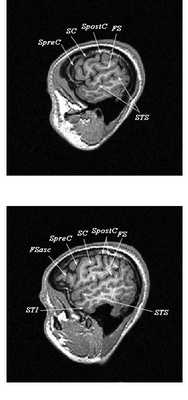

Сагиттальные МРТ срезы головного мозга

МРТ головного мозга. Трехмерная реконструкция латеральной поверхности коры.